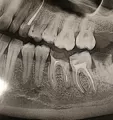

У меня 36-й зуб давно депульпирован, 15 лет назад. Каналы пролечены плохо, как видно по снимку. Стенки разрушены. Каковы шансы на его сохранение? Если шансы сохранить, велики, то его можно покрыть вкладкой и коронкой?

• Осталось очень мало собственных тканей и ещё много поражённых тканей уйдёт при препарировании зуба. Также по снимку у верхушек корней зуба есть очаги воспаления. Поэтому, скорее всего, зуб подлежит удалению, так как гарантий на успешное перелечивание нет. После удаления дефект можно заместить или имплантатом или мостовидным протезом с опорой на 5 и 7 зубы.

На панорамном снимке два зубы выделенные красным, я так полагаю их нужно перелечивать каналы. Возможно сохранить зубы не удаляя?

• По данному рентгеновскому снимку, за верхушками корней 17-х и 46-х зубов есть воспалительные процессы небольших размеров. Гарантий на успешное эндодонтическое перелечивание нет (успех зависит не только от врача, но и от резистентности организма человека). Попробовать перепломбировать корневые каналы можно, так как жевательные зубы лучше сохранить. Проконсультируйтесь очно со читать далее